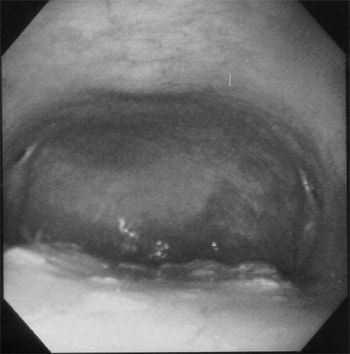

Hematuria can be a presenting complaint for a variety of disorders of the urinary tract. The problems causing hematuria can range from relatively minor disorders to more severe disease processes that may result in life-threatening hemorrhage.